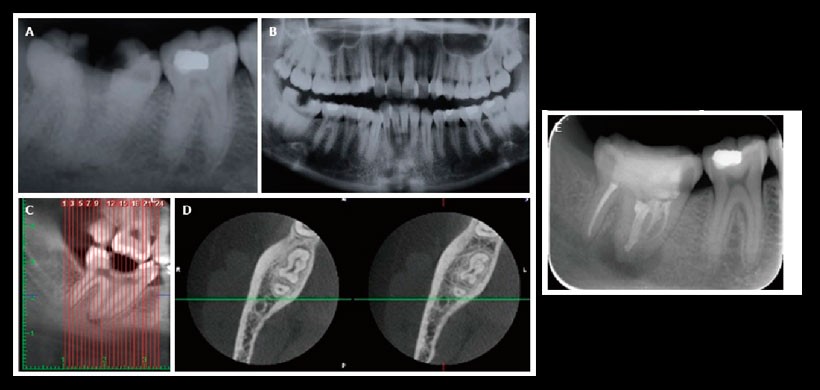

Fig 5. La valoración radiológica del segundo molar mandibular derecho. A: En la radiografía periapical, se detectó la presencia de caries y una lesión periapical en un diente mandibular derecho fusionado con el segundo molar; B: se visualiza una aparente fusión de la pieza 4.7 con la pieza 4.8 C. Reformación panorámica de la CBCT D. Vista axial, mostraron que el segundo molar mandibular y el tercer molar estaban fusionados; E: El diente fue re-evaluado seis meses más tarde con la radiografía periapical luego del tratamiento de conductos.